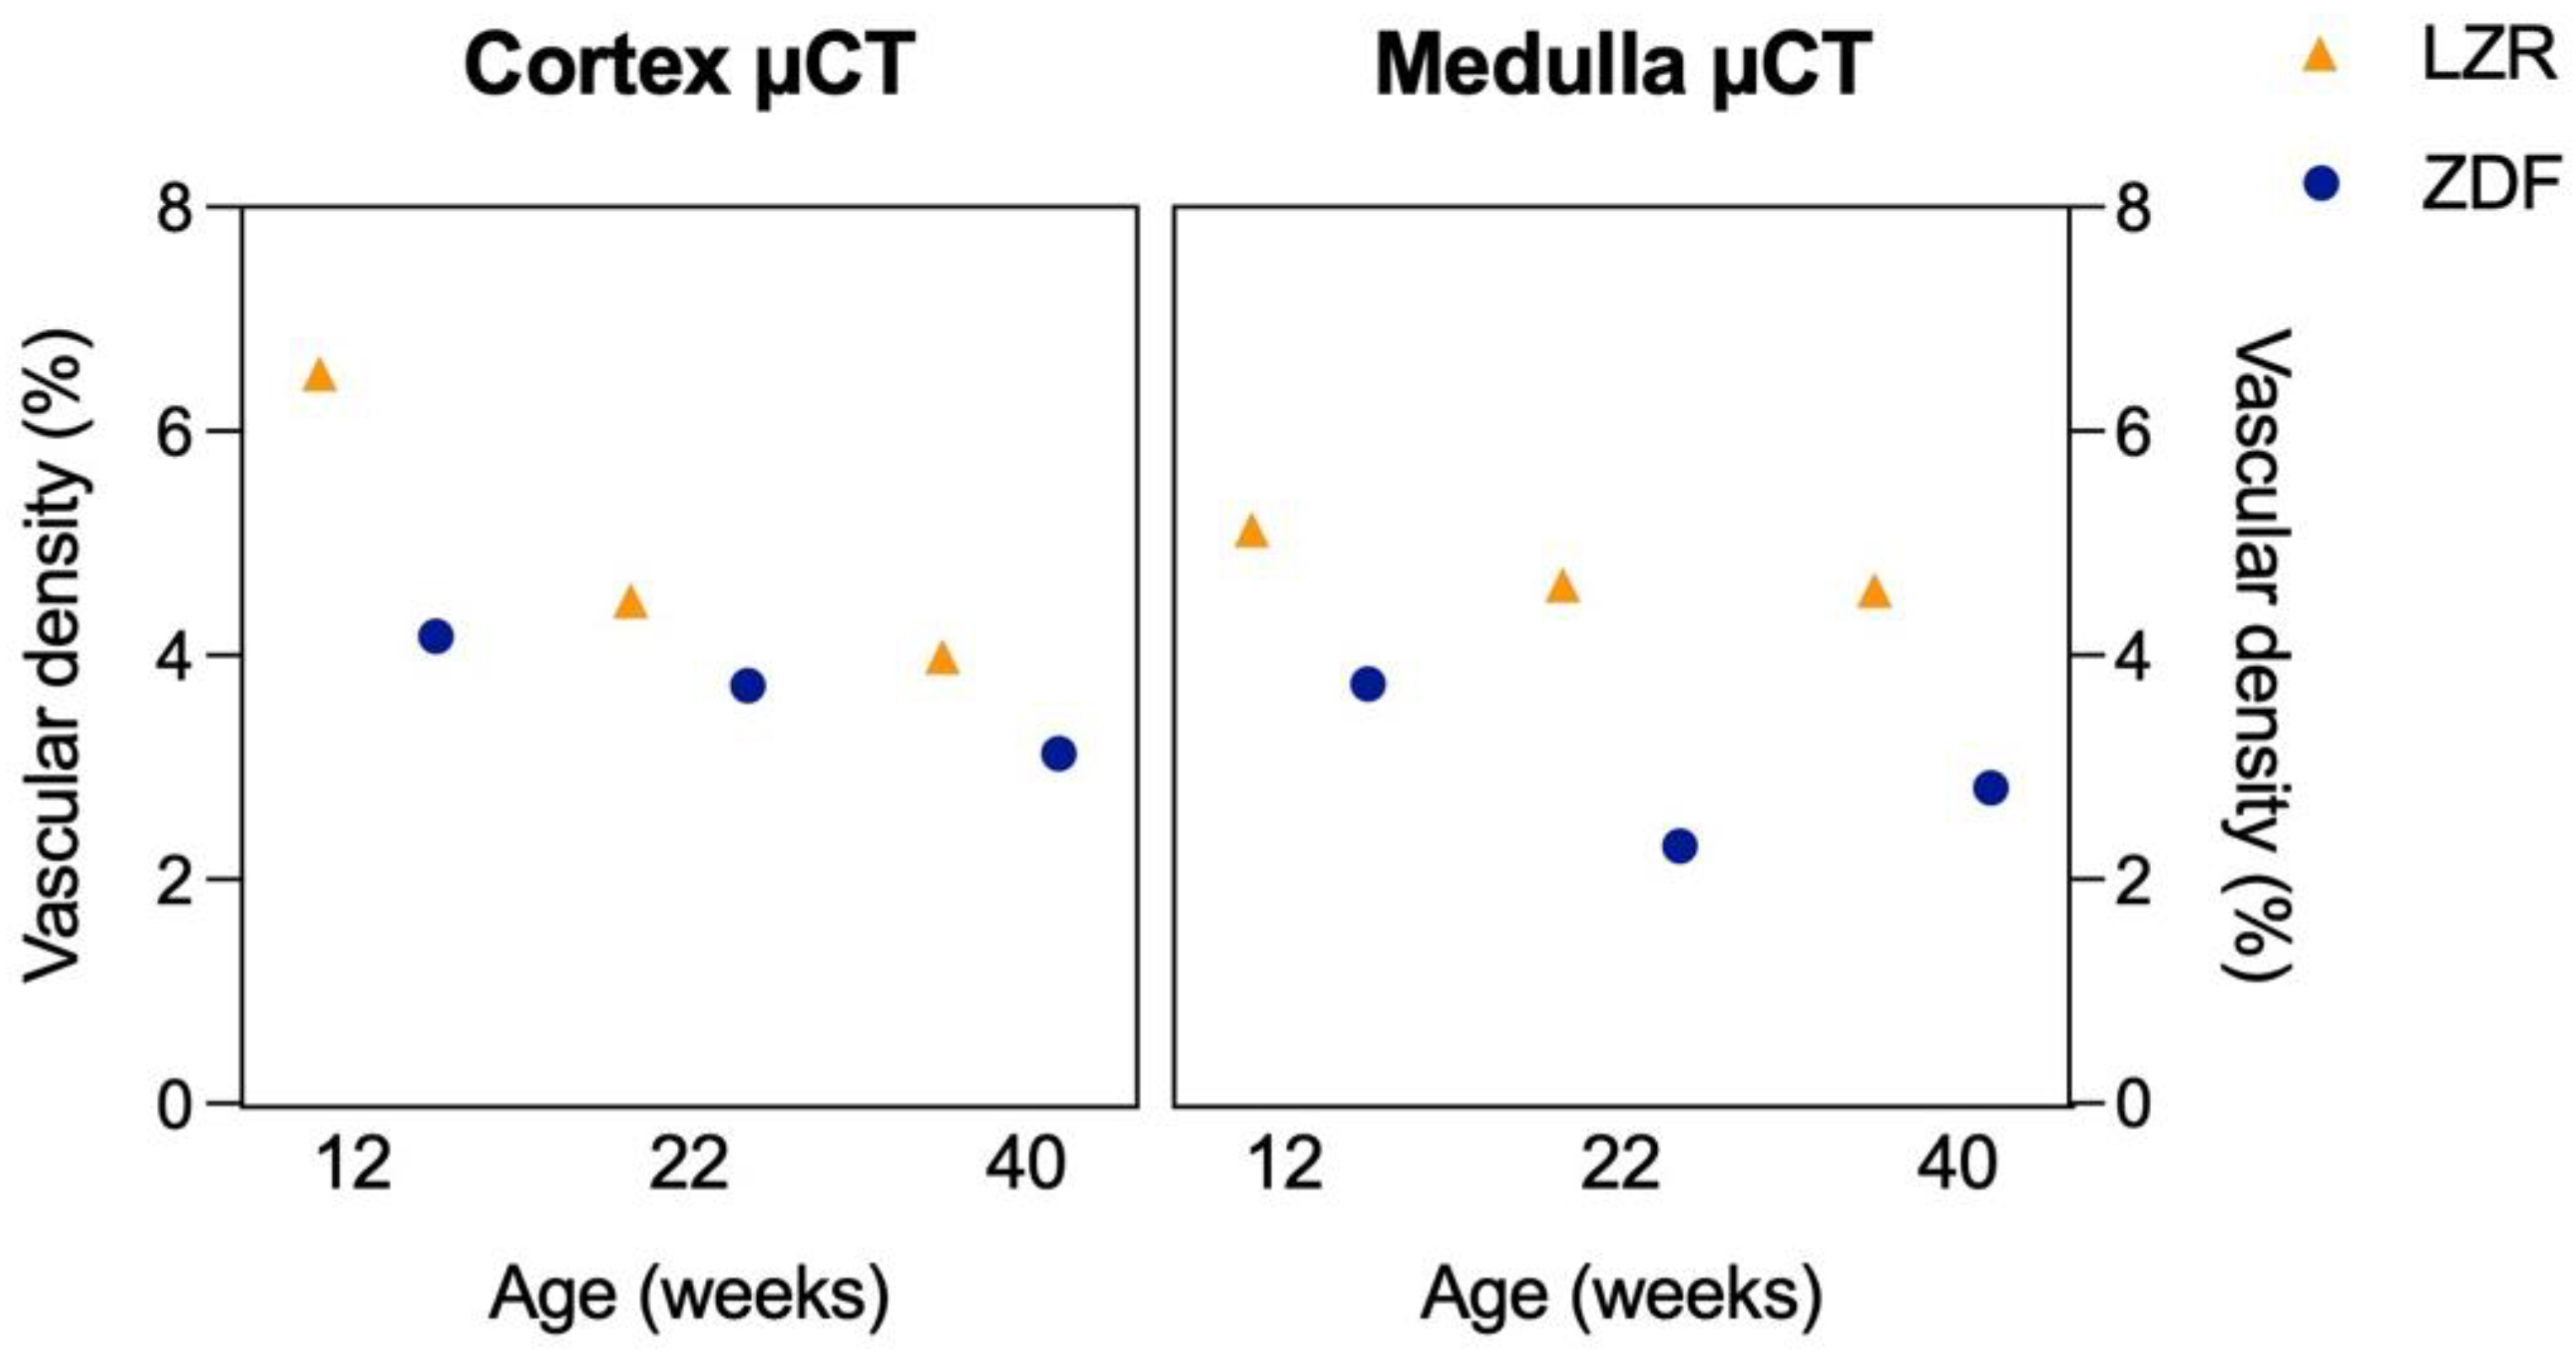

3.4. Qualitative and Quantitative Assessment in µCT